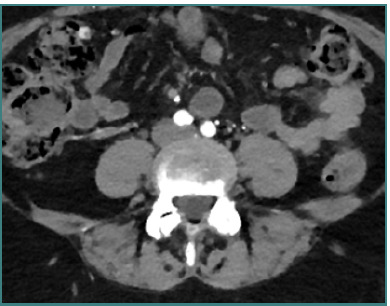

Vascular injuries during anterior lumbar interbody fusion (ALIF) are reported in the existing literature with an incidence rate ranging from 1% to 24%, predominantly venous lacerations owing to branch vessel avulsions during mobilization and retraction. Arterial injuries, although less frequent, occur at an incidence of 0.45% to 1.5% and are mainly characterized by thromboses; aortic lacerations remain exceptionally rare. L4-L5 and L5-S1 are the two levels associated with the majority of vascular complications. Preoperative 3D CT angiography is paramount and a gold standard, as it illustrates the anatomic variations of the iliolumbar vein, the aorta, and the vena cava bifurcation, providing the surgeon with valuable information regarding operative trajectories. Regarding preventive measures, venous laceration, the most common vascular injury, occurs less frequently when employing nonthreaded interbody grafts such as iliac crest autograft or femoral ring allograft. Also, left iliac artery thrombosis can be decreased intraoperatively by intermittent release of retraction. Managing vascular complications includes compression for bleeding control, Trendeleburg positioning of the patient and venorrhaphy, and the employment of topical clot-forming enhancement and/or hemostatic agents. Although postoperative lower limb duplex ultrasonography can be an effective tool, magnetic resonance venography (MRV) and intravenous catheterization (IVC) remain the gold standards for diagnosing postoperative pelvic vein thrombosis in cases of iliac vein repair after anterior spine surgery. This paper aimed to highlight the incidence of major vascular injury during ALIF surgery, describe predisposing risk factors, and discuss management techniques while highlighting the requirement for more sensitive and factor-specific studies to attain a more profound understanding of the mechanism of vasculature complications during ALIF procedures.